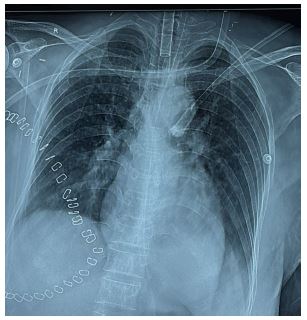

During the preoperative evaluation, the ECG and 2D echocardiogram were normal (Figure 1). However, the patient’s condition later deteriorated with an increased dose of noradrenaline and vasopressor support, and a Point-of-Care Ultrasound (POCUS) examination revealed hypokinesia in both the apical and mid-regions of the heart, along with apical ballooning, indicating left ventricular dysfunction (Figure 2). A cardiologist subsequently confirmed these findings. The blood gas analysis showed metabolic acidosis with a lactate 3 mmol/lt. Further investigations are shown in Table 1.

In the postoperative period, the high-sensitivity troponin I level was 779.9 ng/L, well above the normal upper limit of 19 ng/L. Chest X-ray appears normal as shown in (Figure 3).

Figure 1: Pre-op-ECG Post-op ECG showing ST- T change.

Figure 2: Arrow depicting apical ballooning and hypokinesia.

Figure 3: Chest X-ray of the patient in the postoperative period showing clear lung field.